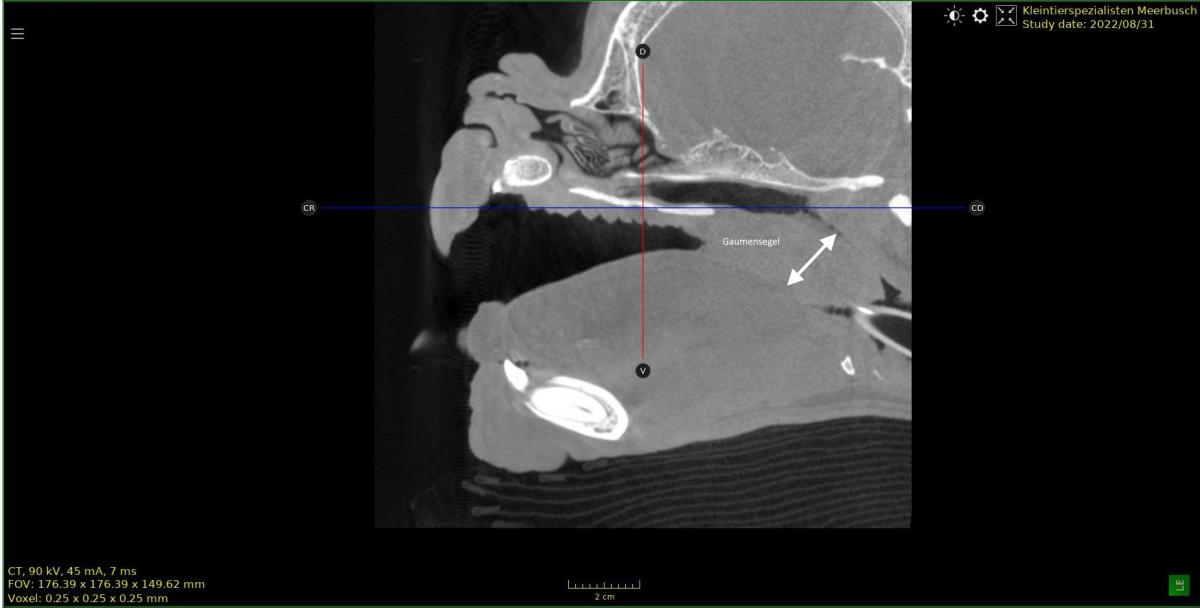

Einkürzen, ausdünnen und falten des Gaumensegels. (folded flap palatoplastie)